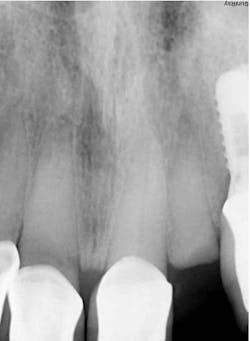

- Radiographic findings: Fractured lateral incisor with periapical pathology

- Clinical findings: Oblique fracture no. 10 to bone level

- Diagnosis: Unrestorable maxillary lateral incisor